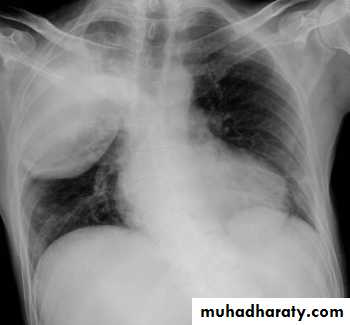

Right upper lobe consolidation

RUL consolidation will be seen as an increased opacity within the right upper lobe. Opacity may be sharply bordered by the horizontal fissureSome loss of outline of the upper right heart border may be apparent

Radiological sign in chest radiograph

Dense opacity seen above the horizontal fissure.

Air-bronchogram line

The lower border of the consolidation is sharply delinated by the horizontal fissure suggesting it lies in the anterior segment of the RUL

RT UL Consolidation